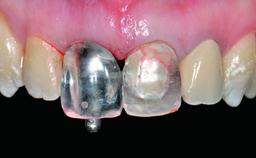

Provisional Implant-Supported Prosthesis Prosthodontic margin > 3 mm apical to mucosal margin Prosthodontic margin > 3 mm apical to mucosal margin

Interim Prosthesis during Healing Fixed Fixed